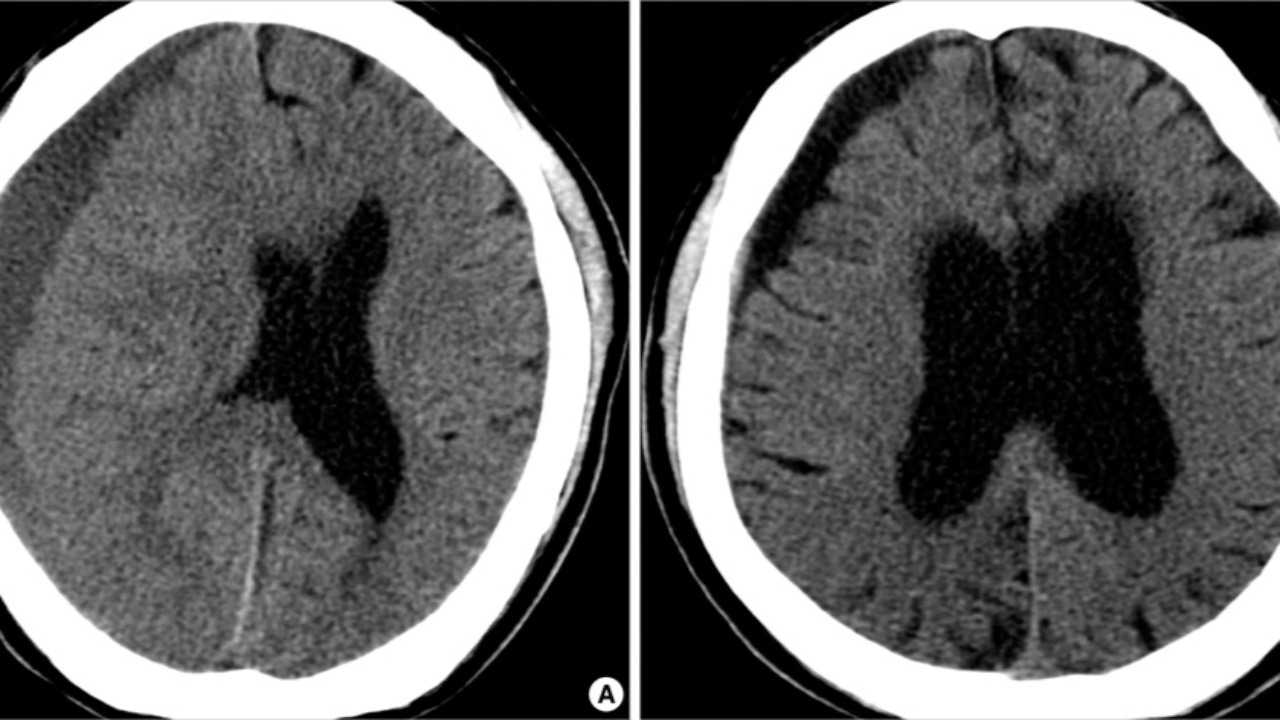

Diagnosis and Medical Imaging:

Brain atrophy is typically diagnosed using imaging techniques such as Magnetic Resonance Imaging (MRI) or Computed Tomography (CT) scans. These scans provide detailed images of the brain, helping doctors assess the extent and location of the atrophy.